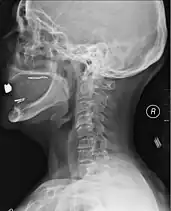

X-rays (left) are more available, but can miss details like herniated disks that MRIs can show (right).[60]

A radiographic evaluation using an X-ray, CT scan, or MRI can determine if there is damage to the spinal column and where it is located.[15] X-rays are commonly available[60] and can detect instability or misalignment of the spinal column, but do not give very detailed images and can miss injuries to the spinal cord or displacement of ligaments or disks that do not have accompanying spinal column damage.[15] Thus when X-ray findings are normal but SCI is still suspected due to pain or SCI symptoms, CT or MRI scans are used.[60] CT gives greater detail than X-rays, but exposes the patient to more radiation,[62] and it still does not give images of the spinal cord or ligaments; MRI shows body structures in the greatest detail.[15] Thus it is the standard for anyone who has neurological deficits found in SCI or is thought to have an unstable spinal column injury.[63]